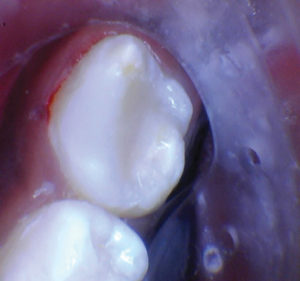

Figura 2. La exposición pulpar se produjo al excavar la dentina infectada (la exposición pulpar no se capturó en la foto). |

Figura 3. Después de quitar el techo de la cámara pulpar. |

Figura 4. Después de excavar el tejido pulpar en los orificios del canal, se utilizó una prenda de algodón seco para evaluar la salud de la pulpa mediante la aplicación de hemostasia por presión. |